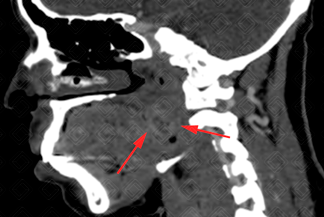

Texto alternativo para a imagem Figura 2. Créditos: Dra. Elazir Mota/ Rio de Janeiro - RJ

Descrição das figuras 1 e 2: Tomografia computadorizada de pescoço após a injeção do meio de contraste. Imagens axial e sagital evidenciando aumento de volume da região peritonsilar à esquerda, com impregnação heterogênea, caracterizando pequena coleção deste lado (setas vermelhas), medindo cerca de 2,0 x 1,5 cm, reduzindo discretamente a coluna aérea faríngea.